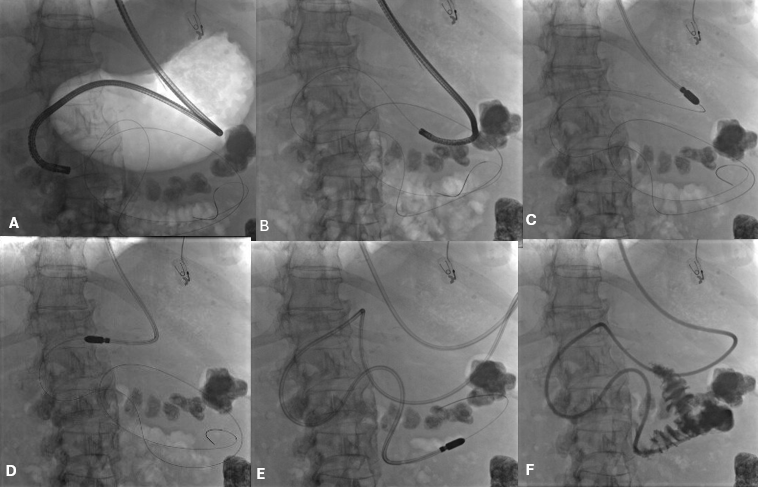

An Overview of Segmental Bile Duct Dilation and Caroli’s Disease

The biliary system is responsible for transporting bile from the liver and gallbladder to the small intestine to aid in digestion. It consists of a complex network of ducts that can be affected by myriad disorders. One uncommon abnormality is segmental, or focal, dilation of the bile ducts. This refers to cystic dilatation of portions […]